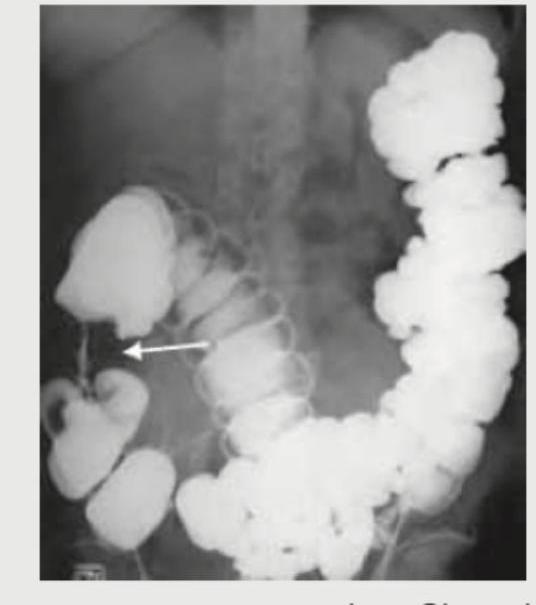

Comment on the diagnosis of the image shown below.

Explanation: ***Coffee bean appearance*** - The image depicts a **dilated loop of colon**, characteristic of a **sigmoid volvulus**, which often resembles a coffee bean on plain abdominal radiographs. - This appearance is due to the **mesentery twisting around the bowel**, causing the dilated loop to fold upon itself. *Apple core appearance* - This describes a **constricting lesion** in the bowel, typically seen in **colorectal cancer**, where the lumen is severely narrowed with overhanging edges. - It denotes an **irregular, circumferential narrowing**, which is not seen in the provided image. *Claw sign* - The **"claw sign"** in the context of imaging refers to the way normal kidney tissue appears to "clasp" or surround an adjacent mass. - This sign is used to distinguish between intrarenal and extrarenal masses, which is irrelevant to the bowel pathology shown. *String sign of Kantor* - The **Kantor's string sign** is a radiologic finding in which the lumen of the terminal ileum is markedly narrowed, appearing as a thin, continuous string of barium. - This is classically associated with **Crohn's disease**, signifying severe inflammation and fibrosis, and is not seen in this image.